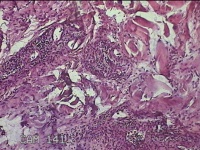

左侧腰部皮肤息肉组织

性别

男

年龄

40岁

临床诊断

皮肤和皮下组织良性脂肪瘤样肿瘤,其他部位的

一般病史

发现左侧腰部皮肤息肉组织5年余。

标本名称

大体所见

灰白暗红色息肉样组织1.7x1.3x0.3cm一块,表面糜烂,切面灰白暗红色,质软。